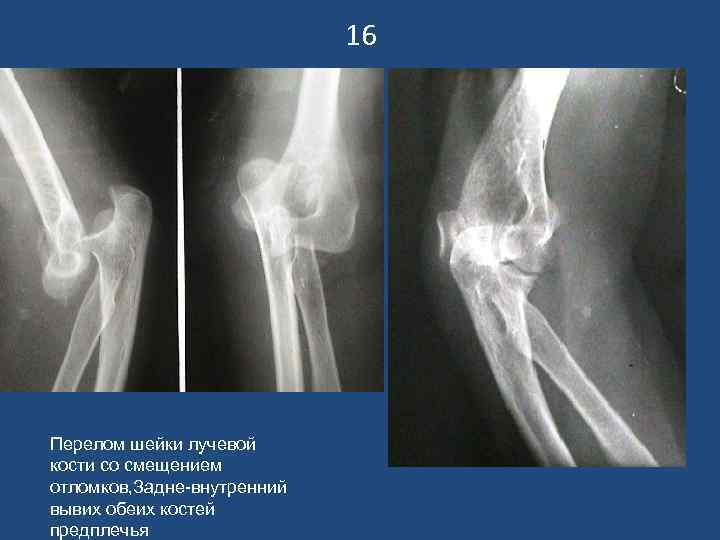

16 Перелом шейки лучевой кости со смещением отломков, Задне-внутренний вывих обеих костей предплечья